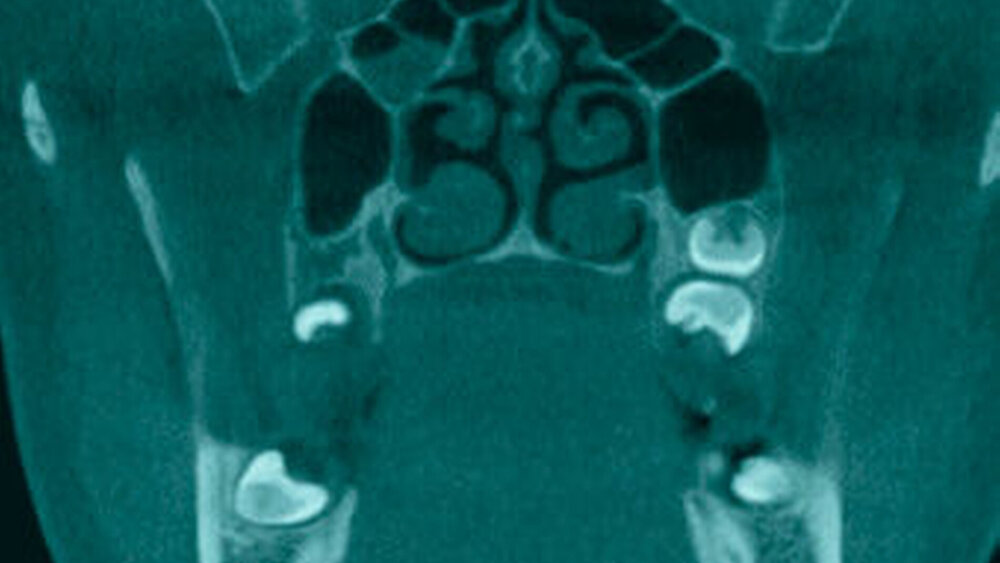

In der Aufnahme konnte distal des Zahnes 28 ein überzähliger Zahn 29 dargestellt werden (Abbildungen 2 und 3). Zudem zeigte sich eine diskrete Schleimhautschwellung in den Sinus ethmoidales auf der rechten Seite (Abbildung 6) sowie eine Concha bullosa (Abbildung 5). Zudem zeigten sich korrespondierend zum OPG die retinierten und verlagerten Zähne 18, 28, 38 und 48 (Abbildung 2). Überraschenderweise konnte kein Distomolar distal 18 beschrieben werden (Abbildung 4).

Weiterhin schloss das DVT eine Kieferhöhlenverschattung aus, stellte jedoch eine diskrete Verschattung der rechten Ethmoidalzellen sowie eine Concha bullosa als Nebenbefunde dar. Diese potenziell pathologischen Befunde geben Anlass zu einer erneuten Anamnese und klinischen Überprüfung im Verlauf.